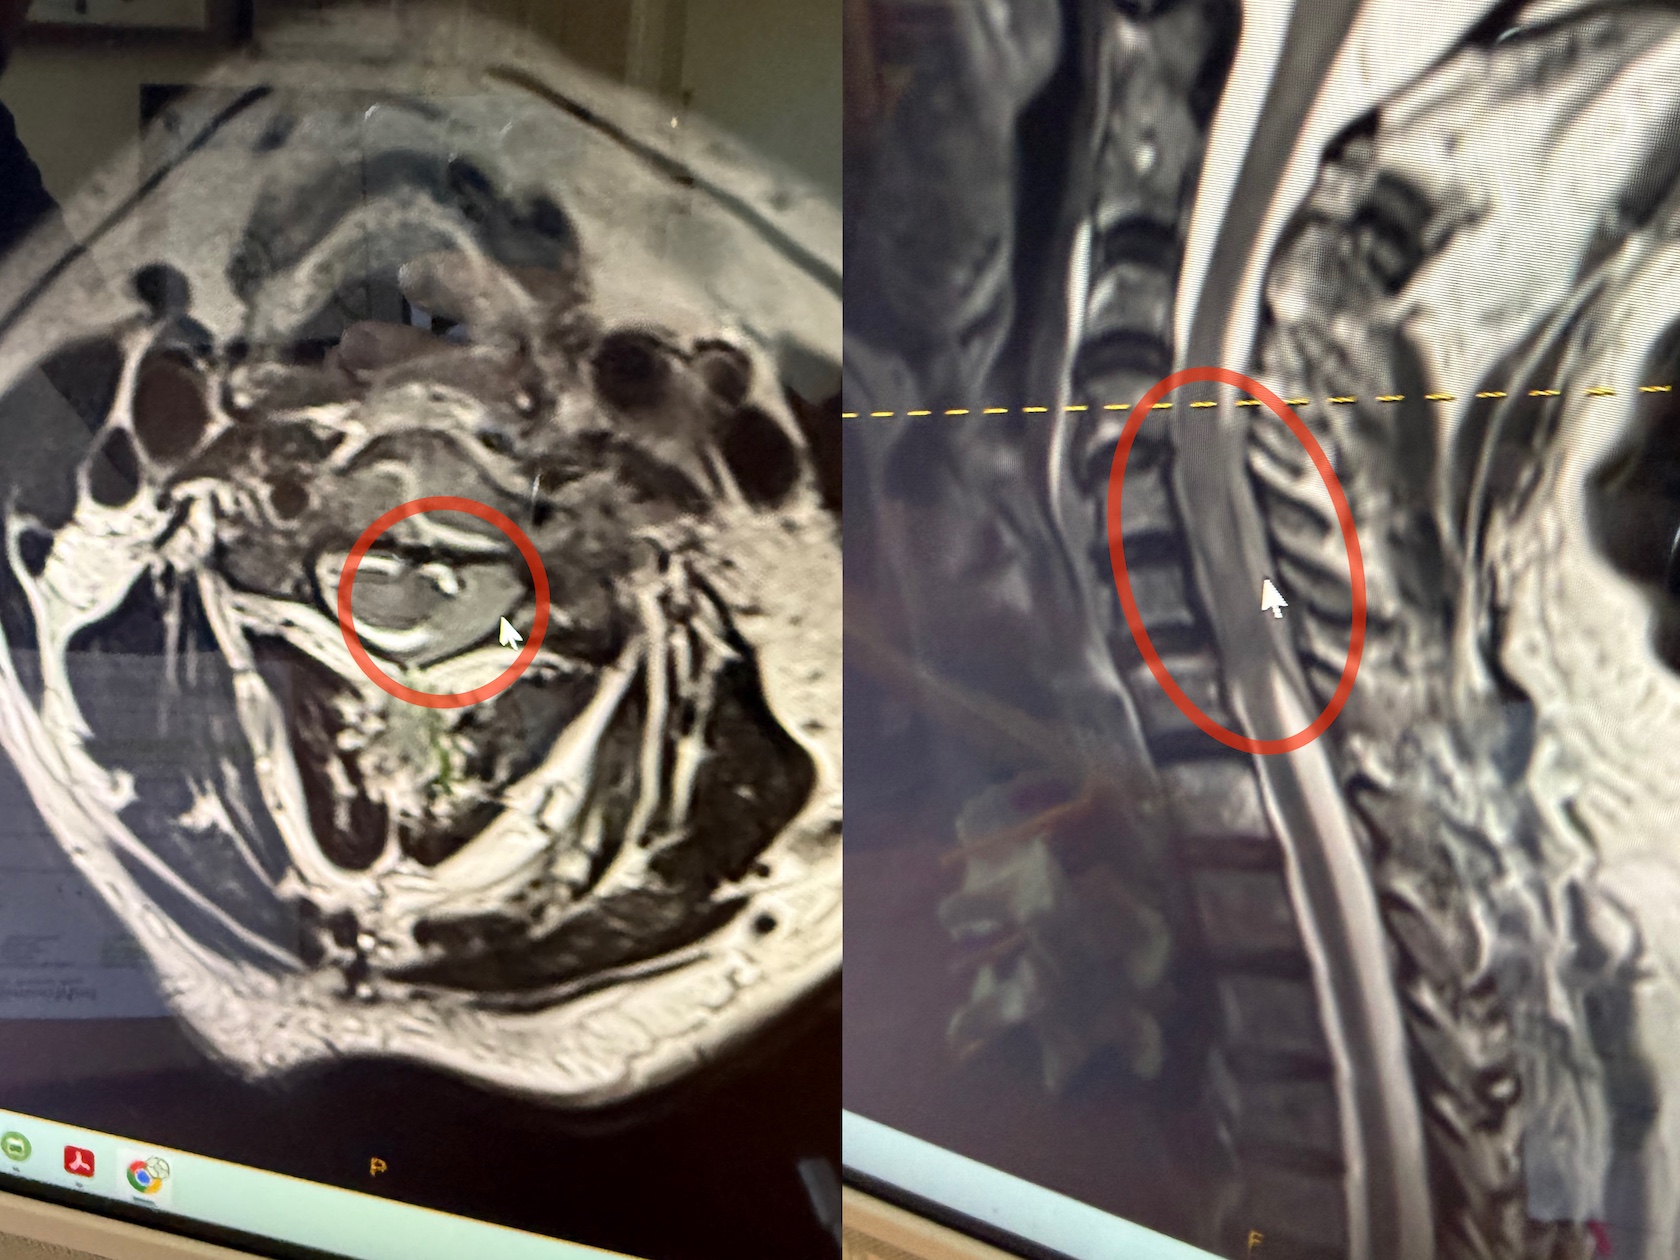

My primary care physician prescribed muscle relaxers which had no effect. My chiropractor scheduled an MRI on the 14th and we got the results on the 17th.

The MRI showed that I had a mass in my spine that was pressing on the fluid that protects and nourishes the spinal cord. My neck was screwed up more than anyone expected and needed immediate attention. A referral to oncology at Hoag Hospital got us into the ER on the 19th.

All the tests confirmed the spinal mass and provided a plan for treatment. I was given steroids to reduce inflammation and felt immediate relief: it was the first time I had been without neck pain in about eight months. Next, a cervical laminectomy would remove part of my spine and permanently relieve the pressure on the spinal cord that was the source of my pain. It would also allow the doctors to obtain a sample for pathology: to determine if the mass inside my spine was benign or malignant.